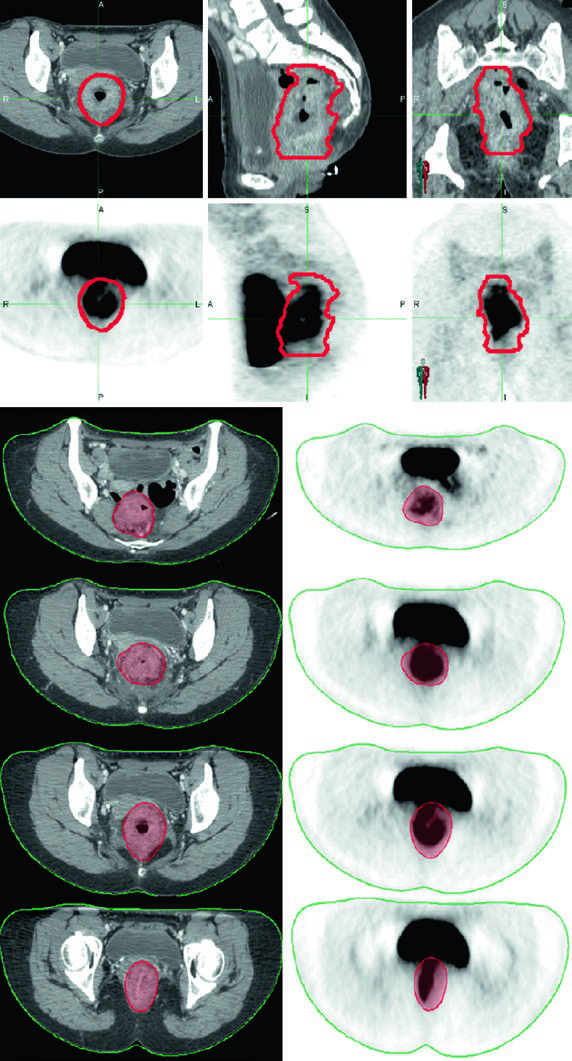

O PET/CT pode auxiliar no delineamento da doença macroscópica, mas áreas de baixa captação do radiotraçador não devem se sobrepor aos achados do exame físico, endoscopia ou CT/RM. Na prática, a fusão de imagens PET/CT com o planejamento é mais útil para confirmar a extensão do GTV do que para substituir os outros métodos de imagem.

A simulação por CT com contraste intravenoso e espessura de corte de no máximo 3 mm é mandatória. Contraste oral pode ajudar a delinear o intestino delgado. A fusão com PET/CT ou RM diagnóstica melhora a precisão do delineamento. O enchimento vesical merece atenção especial: bexiga cheia reduz o volume de alça intestinal na pelve, enquanto bexiga vazia oferece maior reprodutibilidade.

Definição dos Volumes de Tratamento: GTV, CTV-HR e CTV-SR

O GTV primário (GTV-P) engloba toda a doença macroscópica identificada no exame físico, endoscopia e exames de imagem. O GTV nodal (GTV-N) inclui todos os linfonodos perirretais, messorretais e ilíacos comprometidos. Na ausência de biópsia, linfonodos duvidosos devem ser incluídos como GTV. Tumores retais baixos exigem atenção aos linfonodos inguinais, e tumores com invasão anterior em órgãos adjacentes requerem avaliação dos linfonodos ilíacos externos.